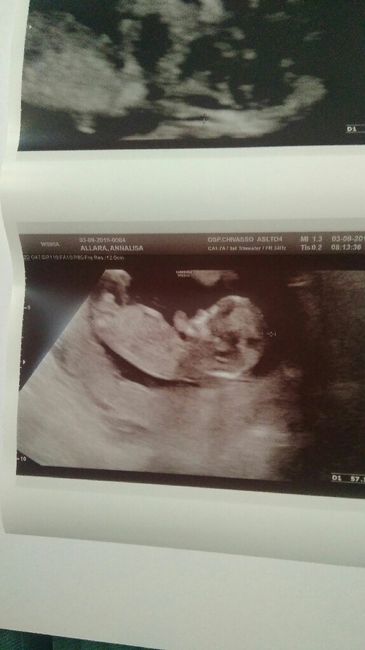

Mancano ancora tantissime settimane alla morfologica, che avrò il 15 Luglio, mi ritrovo spesso a fantasticare se sarà Filippo o Lucrezia, io mi sento maschio ma non si sa mai.

Mi affido a voi esperte di Nub Theory, cosa dite maschio o femmina??